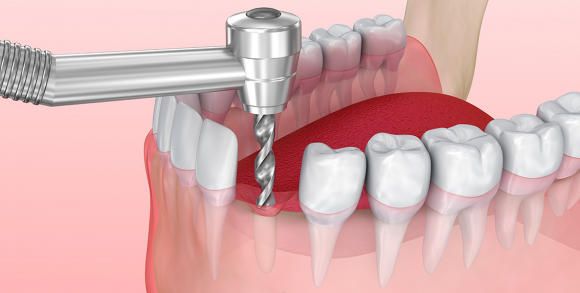

国产种植牙和进口种植牙在质量和价格上有一定的区别,但并不是绝对的大。国产种植牙在技术和质量方面的差距逐渐缩小,一些品牌也取得了一定的技术突破,提升了产品质量。进口种植牙由于需从海外运输并涉及进口环节,其价格较…

种植牙是通过手术方法将种植体(人工牙根)植入牙槽骨内,再在上面安装基台与牙冠来完成缺牙修复的一种高端牙齿修复技术,其中,..._新浪网